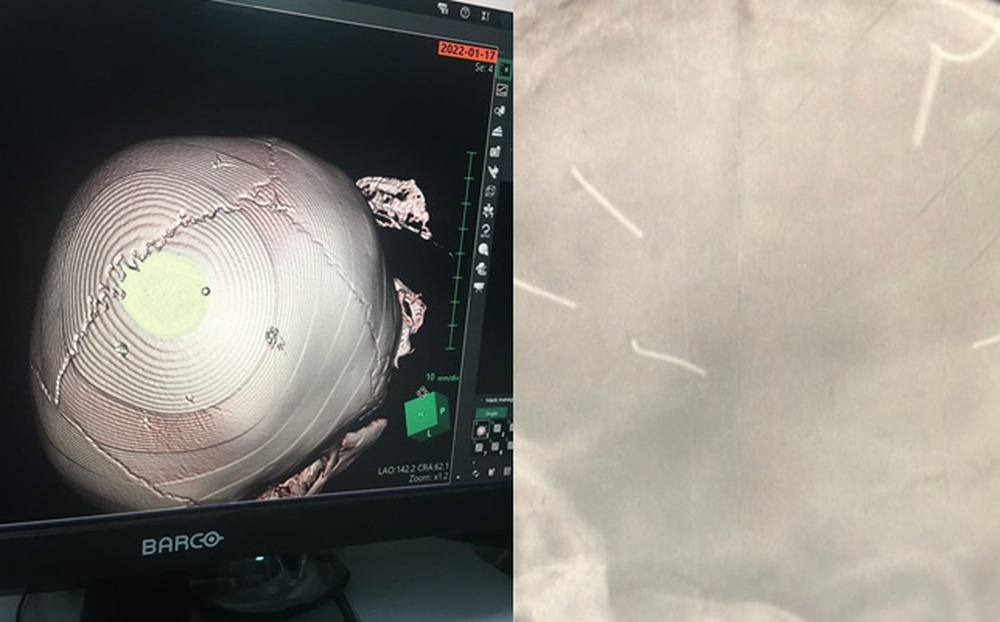

Hình ảnh phim chụp X-quang cho thấy hộp sọ của bệnh nhi có 9 đinh. (Ảnh: BVCC)

Đáng chú ý, tại Bệnh viện Đa khoa Xanh Pôn, kết quả phim chụp cắt lớp cho thấy bệnh nhi Đ.N.A. có hình ảnh như bị đinh bắn vào hộp sọ. “Có 9 chiếc đinh. Bệnh nhân đang trong tình trạng rất nặng, đe doạ tử vong cao”, BS Kiên cho biết thêm.